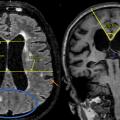

Hydrocéphalie à pression normale

HYDROCEPHALE CHRONIQUE DE L'ADULTE

HYDROCEPHALIE